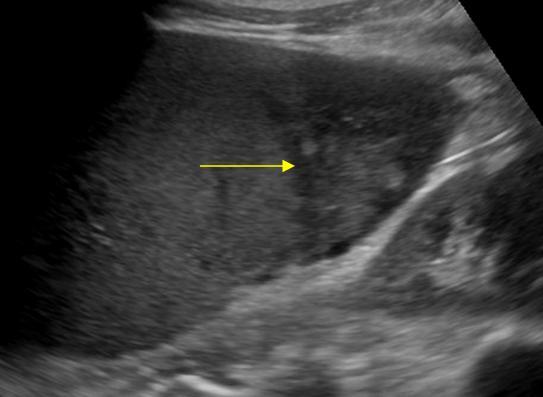

Nhồi máu lách

» Thông tin: Nam giới – 74 tuổi.

» Lâm sàng: Đau mạn sườn trái.